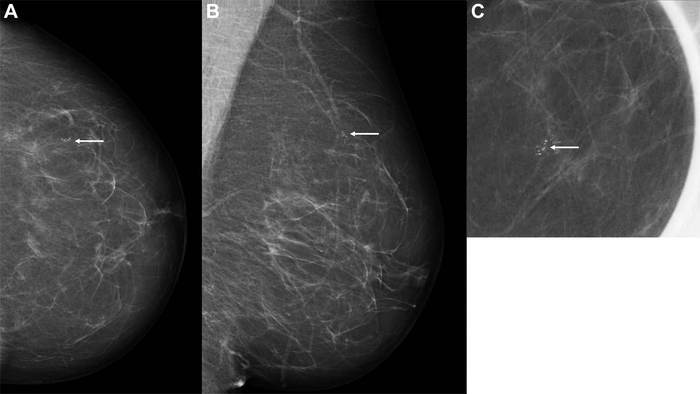

OAK BROOK, Ill. – A major new study in Radiology shows that artificial intelligence (AI) is a promising tool for breast cancer detection in screening mammography programs.

Mammograms acquired through population-based breast cancer screening programs produce a significant workload for radiologists. AI has been proposed as an automated second reader for mammograms that could help reduce this workload. The technology has shown encouraging results for cancer detection, but evidence related to its use in real screening settings is limited.

In the new study—the largest of its kind to date, Norwegian researchers led by Solveig Hofvind, Ph.D., from the Section for Breast Cancer Screening, Cancer Registry of Norway in Oslo, compared the performance of a commercially available AI system with routine independent double reading as performed in a population-based screening program. The study drew from almost 123,000 examinations performed on more than 47,000 women at four facilities in BreastScreen Norway, the nation’s population-based screening program.

The dataset included 752 cancers detected at screening and 205 interval cancers, or cancers detected between screening rounds. The AI system predicted the risk of cancer on a scale from 1 to 10, with 1 representing the lowest risk and 10 the highest risk. A total of 87.6% (653 of 752) of screen-detected and 44.9% (92 of 205) of interval cancers had the highest AI score of 10.

The researchers created three thresholds to assess the performance of the AI system as a decision-making tool. Using a threshold that mirrors the average individual radiologist rate of positive interpretation, the proportion of screen-detected cancers not selected by the AI system was less than 20%. While the AI system performed well, the study’s reliance on retrospective data means that more research is needed.